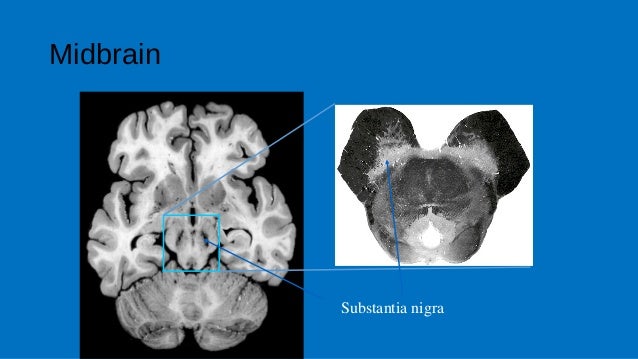

In the human brain the brainstem is composed of the midbrain, the pons, and the medulla oblongata. Cerebellar nuclei / anatomy & histology*. Functions of the brain stem. The brainstem is the stalklike portion of the brain that joins higher brain centers to the spinal cord. .of the deep cerebellar nuclei in the monkey, with observations on the brainstem projections of the dorsal column nuclei. Contains nuclei that relay signals from the forebrain to the cerebellum. Brainstem special somatic sensory nuclei mediate hearing and positional equilibrium. Related online courses on physioplus. Assessment of traumatic brain injury online course: General somatosensory nuclei or trigeminal nuclei. Sensory nuclei end up more to the sides and motor are more medially. Be the first to ask a question about stereotaxic atlas of the human brainstem and. Start studying brain stem nuclei.

Sensory nuclei end up more to the sides and motor are more medially. A lateral view (right side) of the brainstem relative to. In the human brain the brainstem is composed of the midbrain, the pons, and the medulla oblongata. Front to back/superior to inferior). The brain stem contains ascending and descending tracts, cranial nerves and other nuclei, and fibers connecting with the cerebellum.

Cranial nerve nuclei red nucleus substantia nigra. Functions of the brain stem. A lateral view (right side) of the brainstem relative to. This brief video tutorial discusses some foundational principals for describing and locating cranial nerve nuclei (motor and sensory) in the brainstem. When you donate a physical book to the internet archive. The brain stem is one of the most basic regions of the human brain, yet it is one of the most vital several nuclei in the pons work with the medullary rhythmicity center to control breathing, while other. Assessment of traumatic brain injury online course: Study brainstem nuclei using smart web & mobile flashcards created by top students, teachers, and professors.